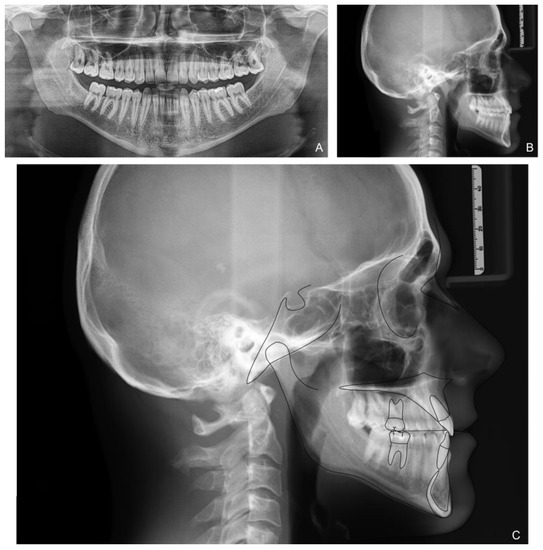

The patient correctly wore the aligners for 22 h a day with class III elastics anchored on the upper first molars and lower canines. After 12 months of treatment, the patient had improved tooth class, a positive anterior overjet, resolution of the posterior crossbite, and improved upper and lower alignment. At the end of the first phase of treatment (Figure 5), slight refinement was required. A few months later, the patient consolidated the molar and canine class I relationship, achieved a positive overjet and overbite, and resolved midline misalignment (Figure 6). At the end of the refinement phase, the patient was required to wear a long-term upper and lower Essix retention device during the night. Due to the transverse discrepancy between the upper and lower arch caused by class III malocclusion, to maintain adequate periodontal health of the upper posterior sectors, it was preferred not to expand the upper arch excessively and therefore not to resolve the crossbite of the second molars. From a cephalometric point of view (Figure 7 and Table 2), the inclination of the lower incisors and interincisal angle improved, which resulted in an aesthetic and functional enhancement. Pre-post-cephalometric evaluation, made with Deltadent® software (Outside format, Pandino, Italy), is reported in Table 3 and cephalometric tracing superimposition is shown in Figure 8.

Figure 7. Patient X-rays and cephalometry after treatment: Orthopanoramic X-ray (A); Latero-lateral skull X-ray (B); Cephalometric tracing (C).

Table 2. Final cephalometric values.

Table 3. Comparison of pre- (t0) and post- (t1) cephalometric values.

Figure 8. Cephalometric tracing superimposition: red line t1 and black line t0.